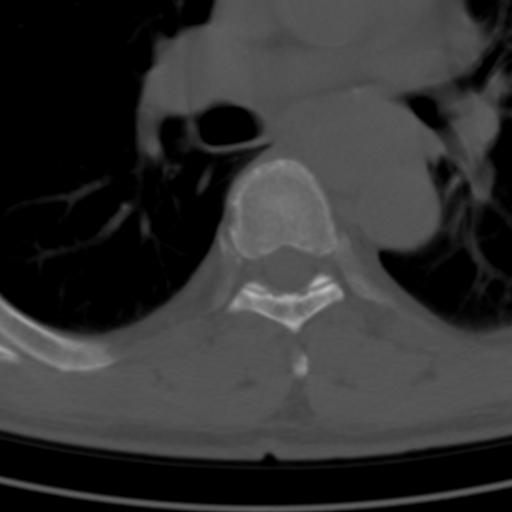

标题: CT25189:胸椎ct,请会诊!

既往食管癌,现行ct检查!

中上段食道癌,椎体轻度退变。

支持中上段食道癌,椎体轻度退变。